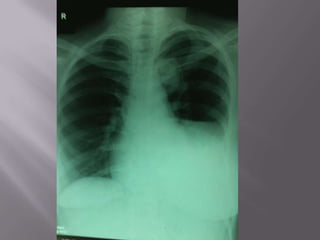

 Invasive thymoma in a young man. (A) Shows a lobular anterior

mediastinal mass associated with a pleural effusion. (B) Image

obtained through the lower chest demonstrates mixed soft tissue

(arrows) and fluid attenuation owing to transpleural spread.